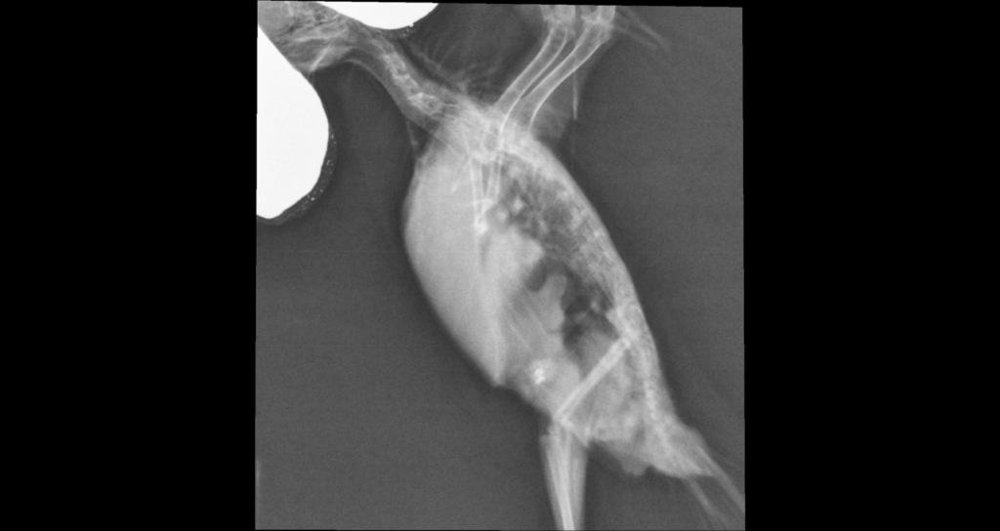

Klyb7nichka Опубликовано 10 мая, 2020 #122 Опубликовано 10 мая, 2020 Привет! У нас у кореллы подозрение на аспергиллез. Снимок выкладываю, может знающие посмотрят? Из симптомов - не ест, пьёт сам редко, вялый, все время спит, началось резко сутки назад помет жидкий Прошу помощи!!!

SilverDrein Опубликовано 10 мая, 2020 #123 Опубликовано 10 мая, 2020 @Klyb7nichka Прямую проекцию делали? Чтобы птица на спине лежала.

Klyb7nichka Опубликовано 10 мая, 2020 #124 Опубликовано 10 мая, 2020 1 час назад, SilverDrein сказал: @Klyb7nichka Прямую проекцию делали? Чтобы птица на спине лежала. Нет, нам почему то не сделали

Klyb7nichka Опубликовано 10 мая, 2020 #125 Опубликовано 10 мая, 2020 @SilverDrein что может быть? Очень переживаю за птицу!

SilverDrein Опубликовано 12 мая, 2020 #126 Опубликовано 12 мая, 2020 @Klyb7nichka Я не знаю. ( Попробуйте написать в ЛС @Zosia и спросить. Но я не уверена, что она много увидит на одной только боковой проекции. Прямая более информативна.